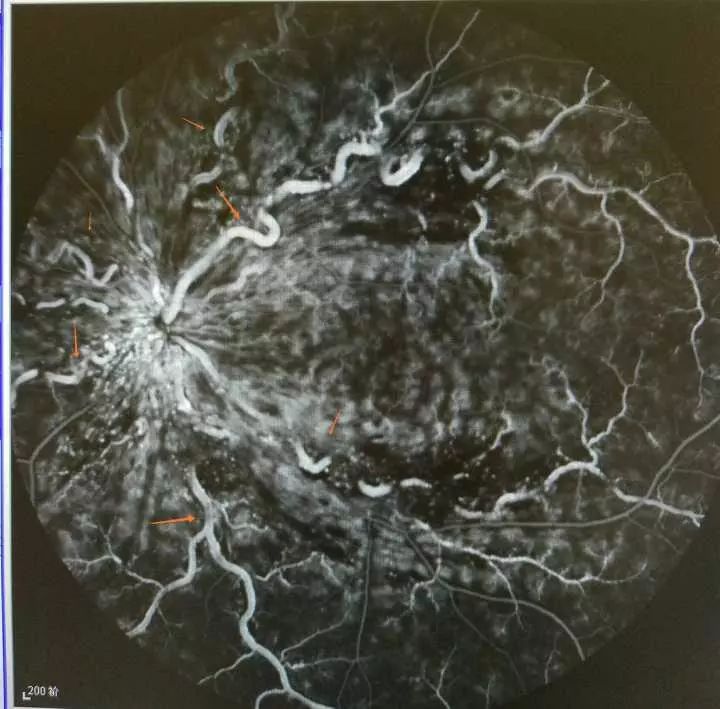

他的右眼患上了视网膜中央静脉阻塞,眼底的血管因阻塞像蚯蚓般扭曲“爬行”,这个总是出现在老年人身上的“眼中风”,原来和小王经常熬夜疲劳有关系。

因为连续一个多星期看东西模模糊糊的,小王就来到浙江省人民医院眼科,眼科主任吴苗琴教授检查后,吓了一跳,小王的眼晴“中风"了,其右眼患上了视网膜中央静脉阻塞。医生看到他眼底的血管因阻塞而变得像蚯蚓般一段段地扭曲“爬行”在眼底出血灶间。

此次复查发现,经过前期的口服药物治疗,眼底出血已有了明显改善,接下来需进行造影检查以及抗水肿治疗和可能相应的激光治疗。不过, 吴苗琴也嘱咐,治疗期间及以后工作生活中,还是要小心,否则影响疗效或加重病情。

小王眼影像图